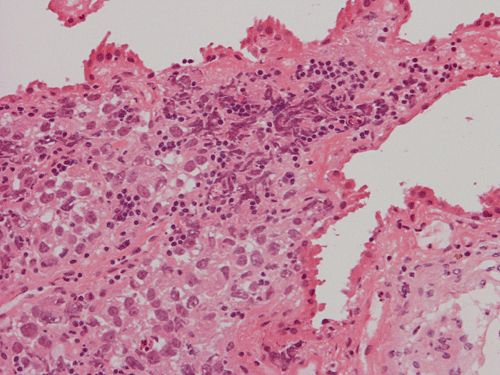

Pathology of the Case: The sample submitted for frozen section has a papillary structure which can be identified as the choroid plexus (Panel C). The center of the choroid plexus is expanded by some large cells accompanied by some smaller cells presumably lymphocytes (Panel D and E). On hematoxylin and eosin stain of the permanent sections, the tumor is composed of clusters of large cells in a background of lymphocytes. On higher magnification, the large cells have enlarged nuclei with prominent nucleoli. No trophoblasts or nor seminomatous component are identified. Immunohistochemistry demonstrated strong positive reactivity for placental alkaline phosphatase (PLAP) (Panel I) and CD117 (c-kit) in the large atypical cells (Panel J). The lymphocytes in the background are strongly immunoreactive for leukocyte common antigen (LCA) (Panel K) but negative for PLAP and CD117.

The discussion here will be limited predominantly to germinoma. Histologically, germinoma has very characteristic features heralded by large, atypical germinoma cells in a background of benign lymphocytes. The germinoma cells are usually huge, with a moderated amount of cytoplasm, and with prominent nucleoli. These cells, even though large, are rarely bizarre. The proportion of germinoma cells with lymphocytes can be highly variable. While most cases show a good mix of both component, the small biopsies yielded by endoscopic biopsy can sample in areas that are lymphocyte predominant or germinoma cell predominant areas which lead to diagnostic pitfalls. It should also be reminded that germinoma has a strong tendency to undergo granulomatous changes. Such granulomatous changes may completely efface the usually big cell-small lymphocyte classic pattern. These biopsies, however, would histologically suggest infection but the clinical history usually would not. Knowing the clinical history is often helpful. Trophoblastic cells could be seen and their presence may indicate a worse prognosis for germinomas. Non-seminomatous component such as embryonal cell carcinoma, yolk sac tumor (endodermal sinus tumor), and choriocarcinoma should also be identified if present.